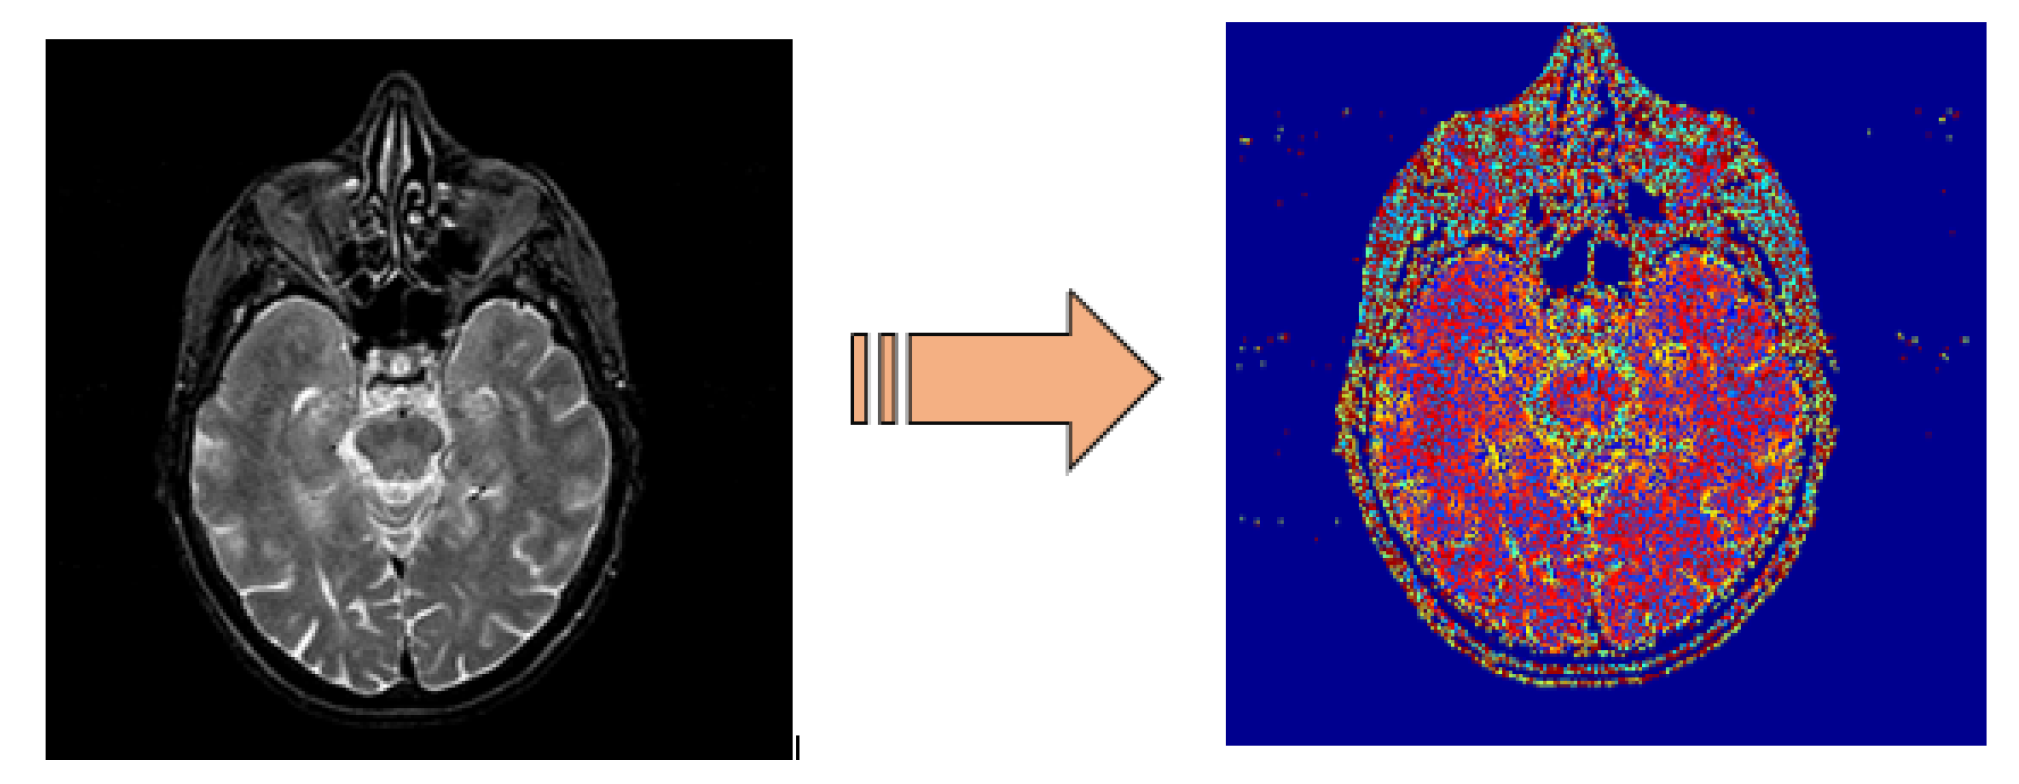

3.2. Discrete Wavelet Transform